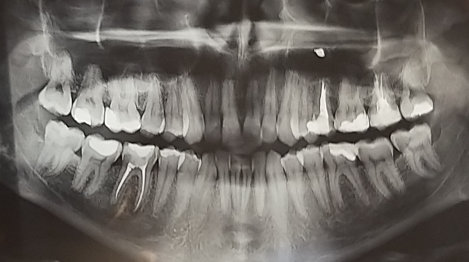

Посетила стоматолога, сделали рентген. Врач сказала, что не уверена что это за пятно на снимке без панорамного снимка. Зуб болит, но на нём откололся кусочек пломбы и образовался кариес. Я думаю, что это гнойный мешок. В ближайшее время планирую посетить еще другого стоматолога, но хотелось бы узнать предположения. Соседний зуб удалили год назад, потому как был гной под зубом и невыносимая боль, а лечение лекарством не помогло.

Вряд ли это костная ткань?

К сожалению, по вашему снимку невозможно определить точно. Вам необходимо сделать КЛКТ снимок и обратиться к специалисту для уточнения диагноза.